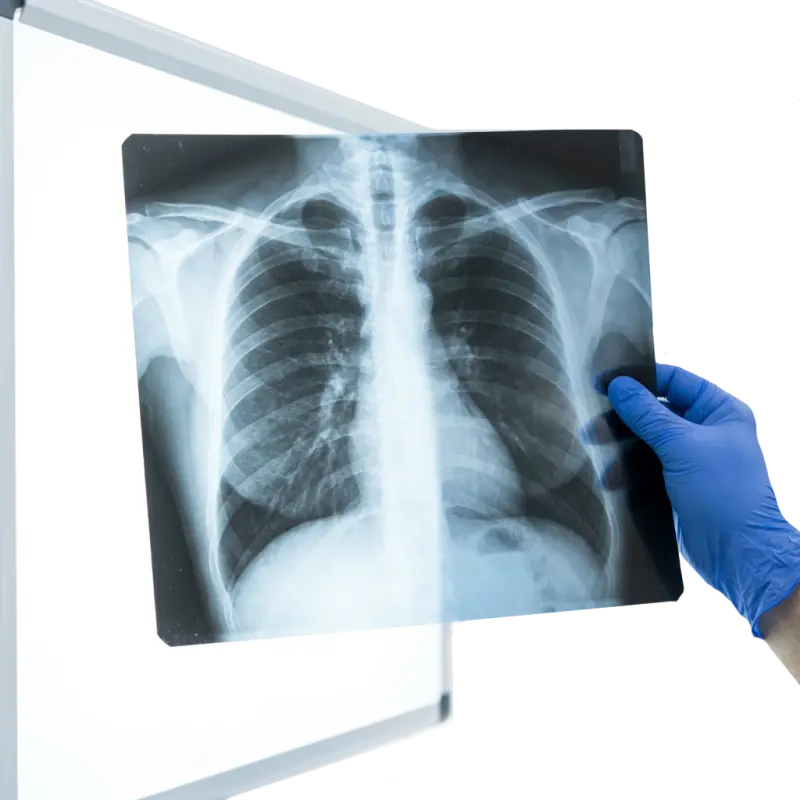

Обязательные медицинские осмотры

Согласно российскому законодательству, иностранные граждане и лица без гражданства, пребывающие в России на долгосрочной основе или с целью работы, обязаны проходить медицинское освидетельствование. С 29 декабря 2021 года это требование (на основании Федерального закона №274-ФЗ) стало обязательным.